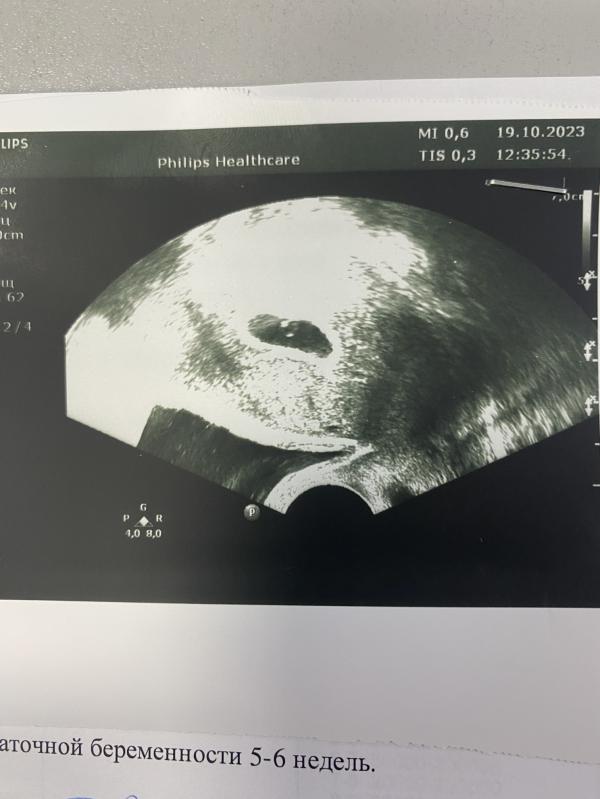

Сегодня подтвердили беременность и сердечко послушали, у нас есть первое фото, как же я счастлива!!!